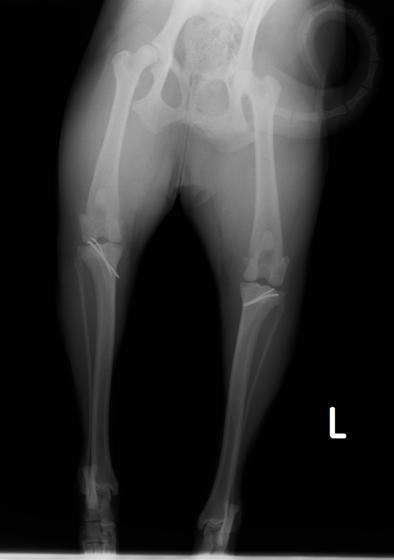

■ 症例20 ポメラニアン 8ヶ月 1.8kg

左右膝蓋骨脱臼 グレードⅢ

2ヶ月前から間欠的跛行が認められ、両膝の膝蓋骨脱臼整復術を行った。

手技は縫工筋及び内側広筋の解放、脛骨粗面の外側転位、滑車ブロック形造溝術、内外側関節包の縫縮を選択し実施した。

右側の膝蓋骨脱臼は上記手技で整復されたものの、左側はそれのみでは膝蓋骨が浮く様子が認められた。その為、PDS縫合糸にて膝蓋靱帯を1糸のみ縫合し、靱帯の縫縮を行った。

膝蓋骨脱臼は膝関節における膝蓋骨の内外側の脱臼と定義されるが、時として単純な内外の脱臼ではなく、膝蓋骨が大きく前方に浮き上がるように脱臼する場合がある。特にトイプードルやポメラニアンといった犬種に多く認められる。

内側脱臼に加えて前方への浮き上がりを矯正する為に、従来より脛骨粗面転移により膝蓋靭帯を外方と下方に引っ張り、固定する方法を選択する。膝蓋骨の前方への浮き上がりが軽度の場合は、従来法ではなく関節包の縫縮で対応していた。しかし、一部の症例で膝蓋骨の動きが悪くなり伸展機構が円滑に機能せずロボット様歩行になるケースがあった。

その為、膝蓋靭帯自体を縫縮する方法を採用した。この方法により、膝関節の伸展機構を妨げず膝蓋骨の軽度の浮きを矯正することが可能となった。

本症例の経過は良好である